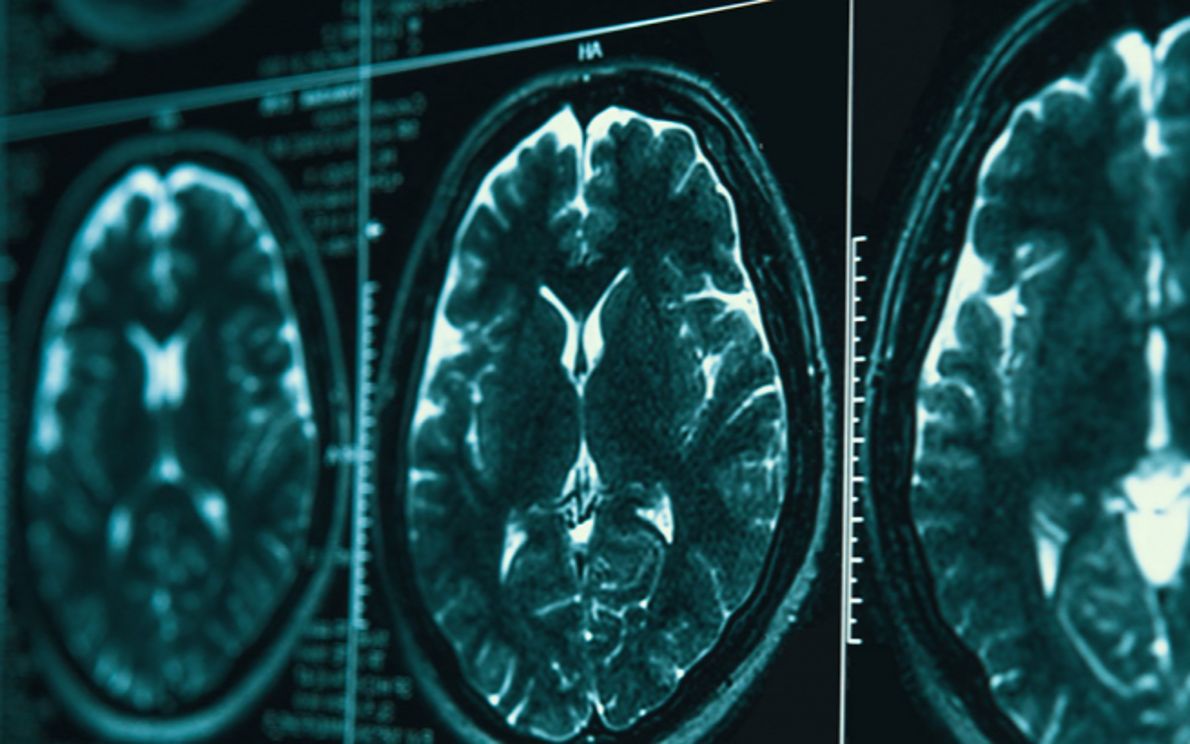

Le connessioni cerebrali, ovvero il modo con il quale le varie aree del cervello comunicano tra loro, possono aprire una nuova via nella lotta all'Alzheimer. A proporre questo cambio di prospettiva è lo studio internazionale guidato dall'Italia con l'Università di Padova, al quale ha contribuito anche l'azienda Chiesi Farmaceutici di Parma. Pubblicata sulla rivista Brain, la ricerca evidenzia, infatti, che oltre le placche di amiloide caratteristiche della malattia, anche le connessioni all'interno del cervello possono essere un importante obiettivo terapeutico e soprattutto una chiave per misurare l'efficacia dei farmaci in via di sviluppo.

"La connettività del cervello è un indicatore sensibile e precoce dei cambiamenti legati all'Alzheimer", afferma il dott. Lorenzo Pini, del dipartimento di Neuroscienze dell’Università di Padova e primo autore dello studio, che ha guidato i ricercatori. "È un approccio che guarda al cervello come a una rete dinamica di connessioni. Un modello che stiamo applicando anche a ictus e tumori, a dimostrazione - aggiunge Pini - di quanto questo paradigma sia trasversale nel campo della neurologia".